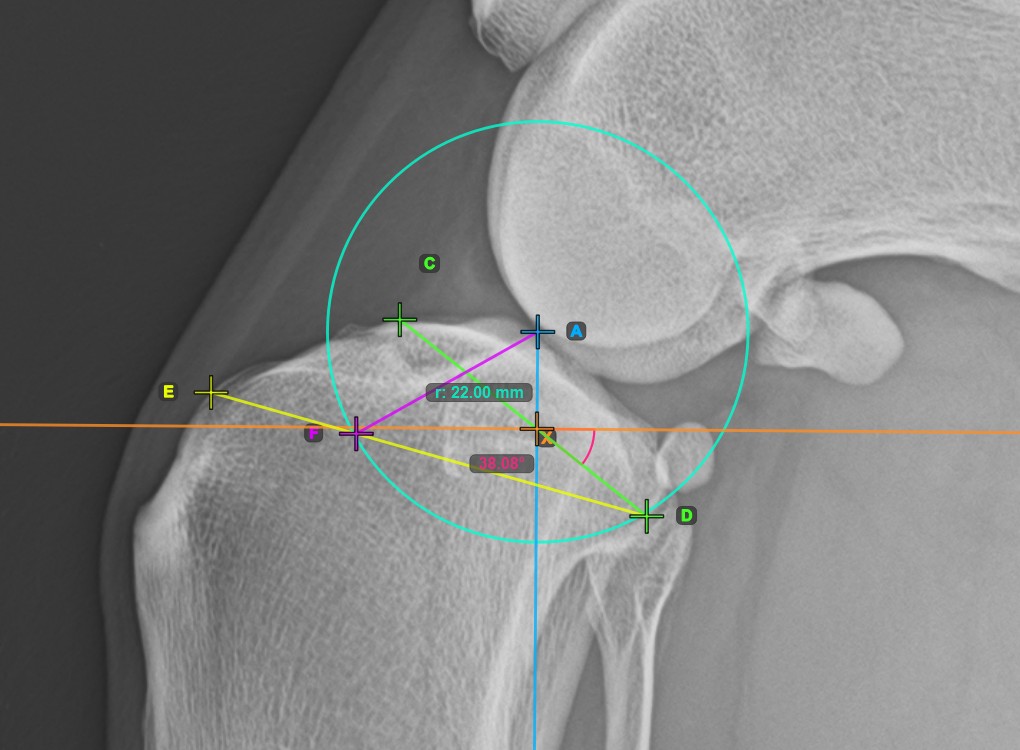

Vervollständigen Sie die TPA-Winkel-Messung, indem Sie den hintersten Punkt des Tibiakopfes (Tibiaplateau) markieren. Der TPA-Winkel wird automatisch als der Winkel zwischen der Linie, die die beiden Punkte am Tibiaplateau verbindet, und der senkrechten Linie zur Längsachse der Tibia berechnet.

Das Bild unten zeigt die übliche Platzierung des hintersten Punkts am Tibiaplateau und die automatisch berechnete TPA-Winkel-Messung.